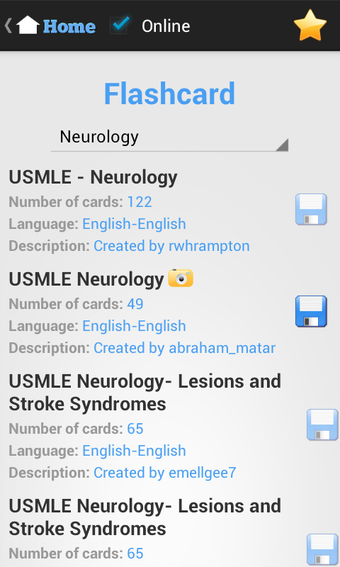

นอกจากนี้ แอปพลิเคชันยังมีการ์ดฝึกหัดเพื่อช่วยให้นักเรียนปรับปรุงคำศัพท์และความรู้ในเชิงการแพทย์ แอปพลิเคชันนี้ใช้ง่ายและวัสดุการเรียนรู้จัดเรียงอย่างดี ทำให้นักเรียนสามารถนำไปใช้ได้อย่างง่ายดาย โดยรวมแล้ว แอปพลิเคชัน USMLE Exam Prep เป็นแหล่งข้อมูลที่ยอดเยี่ยมสำหรับนักเรียนที่กำลังเตรียมตัวสอบ USMLE และเป็นแนะนำอย่างมากสำหรับผู้ที่ต้องการเตรียมตัวสอบอย่างละเอียดและแบบปฏิสัมพันธ์